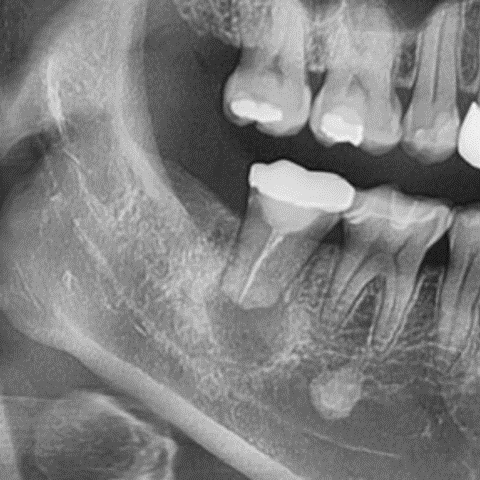

빨간색으로 표시된 부분이 심상치 않아 보입니다.

CT를 찍어봐야겠죠

빨간색으로 보이는 부분은 염증으로 인해 뼈가 녹아 있는 부위,

파란색은 턱과 치아의 감각을 담당하는 하치조 신경입니다.

보시는 것처럼 염증이 신경과 맞닿아 있네요.

이대로 시간이 조금 더 지나면

환자분의 오른쪽 아래턱에 감각이상이 생길 수 있습니다.

즉, 감각이 둔해지거나 무뎌지는 증상이 나타날 수 있다는 뜻이지요.